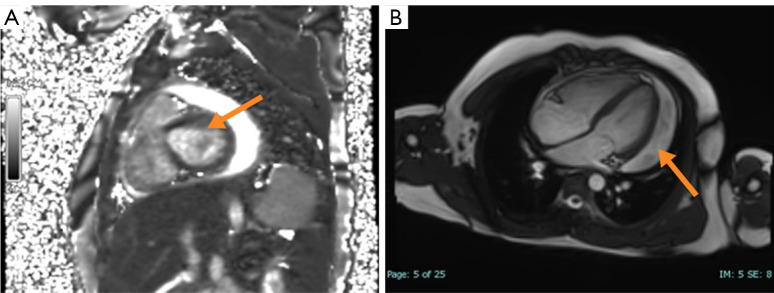

Case description: A 10-year-old boy with confirmed pulmonary paragonimiasis developed refractory pericardial effusion and markedly elevated IgG4 [11 g/L, 8.1× upper limit of normal (ULN)]. Despite five courses of praziquantel (75 mg/kg/day), effusions persisted for 8 weeks. Subsequent glucocorticoids (methylprednisolone 2 mg/kg/day) achieved rapid clinical resolution, though lacked histopathology IgG4-RD hallmarks. Longitudinal monitoring revealed a dynamic IgG4 decline (from 11 to 5.25 g/L) post-methylprednisolone therapy. However, residual IgG4 elevation (5.25 g/L, >3× ULN) and absent histopathological features of IgG4-RD left the diagnosis unresolved. Therapeutic monitoring revealed normalized eosinophils and imaging improvement, yet persistent IgG4 suggested potential immune dysregulation beyond parasitic clearance.